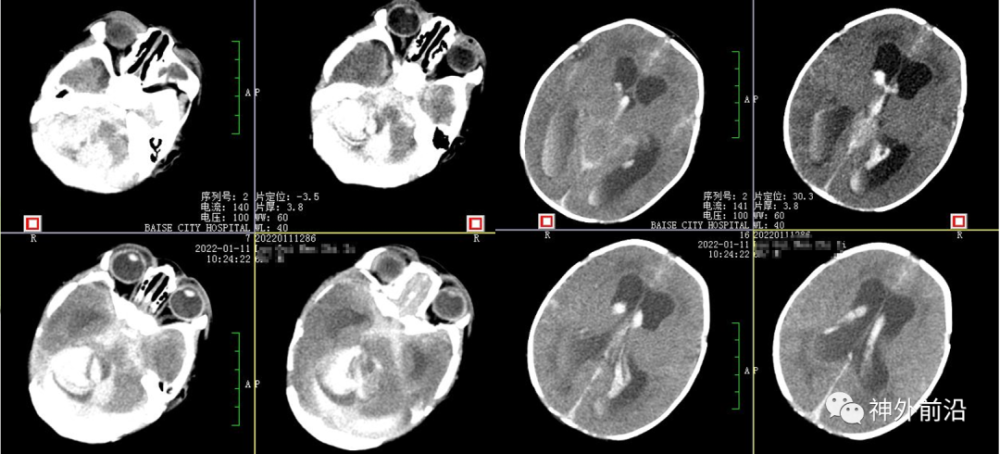

辅助检查:头部CT:两侧小脑半球出血并破入脑室,继发脑室积水。出血量约17ml。

2.术前CT